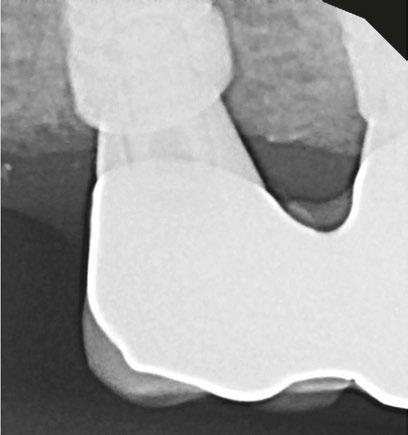

Figure 3: Second maxillary molar with external root resorption (ERR) with incidentally captured ERR on the lower mandibular first molar as well. When there is one tooth with resorption, be suspicious of other teeth with resorption, especially on younger patients Figure 6: No PARL on PA film. Clear PARL on scan taken with medicament Figures 4 and 5: 4. Mandibular molar with a J-shaped lesion due to endo — not a vertical root fracture. Path of least resistance happens to be through a distal perio pocket, but this is an endo-perio lesion and not a VRF. Incidentally, a mucous retention cyst was captured in the sinus. 5. Healing after bridge removal and retreatment

a realistic prognosis. Unfortunately, not all teeth can be saved. Some are not candidates for retreatment (Figure 11). Without a CBCT scan, it would be easy to attempt these retreatments only to discover the true problem mid-treatment, or worse — to think I had caused one (Figures 10 and 11). This added information not only helps the practitioner, but also provides patients a higher level of confidence and trust in you.

With retreatments, maybe the root canal looks completely fine on a PA or panoramic x-ray, but the patient says that it just doesn’t feel right. A cone beam can often reveal the cause of the patient’s discomfort. This could be that the tooth was perforated, cracked or has an unfilled canal, and the patient is totally justified in feeling like something’s wrong. Or sometimes the scan will show that there is another issue on an adjacent tooth or in the patient’s sinuses (causing their discomfort). When patients sense a problem but are told that there is not one (usually based on 2D radiographs), that’s not a great feeling. Being able to show the patient the CBCT scan and say, “You were right, and here’s the issue,” improves the patient experience.